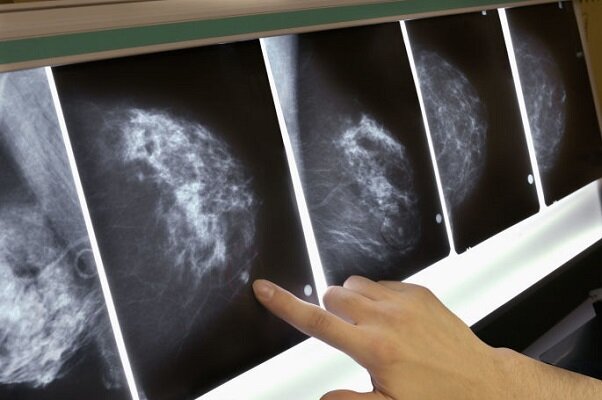

مهر:یک مطالعه شگفتانگیز در سوئیس نشان میدهد که وقتی بیماران مبتلا به سرطان سینه میخوابند، سلولهای تومور ممکن است بیدار شده و از طریق جریان خون پخش شوند.

سالانه حدود ۲.۳ میلیون نفر در سراسر جهان به سرطان سینه مبتلا میشوند. محققان خاطرنشان کردند وقتی سرطان آنها به موقع تشخیص داده میشود، بیماران معمولاً به خوبی به درمان پاسخ میدهند. اما در صورت گسترش سرطان که زمانی رخ میدهد که سلولها از تومور اصلی جدا شده و از طریق رگهای خونی به نقاط دیگر بدن بروند، درمان دشوارتر است.